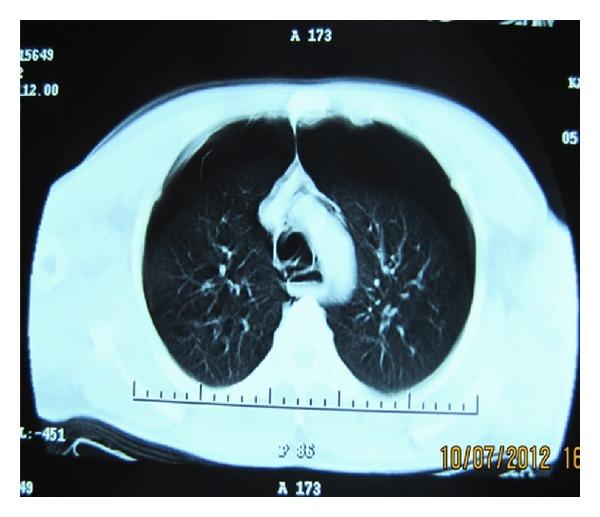

双侧自发性气胸、纵隔气肿和皮下气肿:哮喘罕见且致命的并发症

Bilateral spontaneous pneumothorax, pneumomediastinum, and subcutaneous emphysema: rare and fatal complications of asthma.

Simultaneous bilateral spontaneous pneumothorax (SBSP) and pneumomediastinum are complications rarely observed synchronously during an acute asthma attack. It is a clinical condition that manifests itself with serious respiratory distress and must be rapidly diagnosed and treated. Although bilateral spontaneous pneumothorax has already been reported in asthma patients in the literature, its concurrence with subcutaneous emphysema and pneumomediastinum is extremely rare except for iatrogenic conditions. By sharing this case about a 39-year-old patient who presented to the emergency room with severe respiratory distress and developed cardiopulmonary arrest during his physical examination, our aim is to emphasize that a rapid diagnosis and treatment by the emergency physicians is the only way for survival in these patients.

同时性双侧自发性气胸(SBSP)和纵隔气肿是急性哮喘发作期间很少同时观察到的并发症。这是一种以严重呼吸窘迫为表现的临床病症,必须迅速诊断和治疗。虽然文献中已有哮喘患者发生双侧自发性气胸的报道,但除医源性情况外,其与皮下气肿和纵隔气肿同时发生极为罕见。通过分享这例39岁患者的病例,该患者因严重呼吸窘迫到急诊室就诊,在体格检查期间发生心肺骤停,我们旨在强调急诊医生进行快速诊断和治疗是这些患者生存的唯一途径。